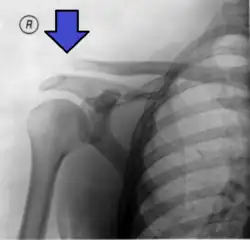

Type 3 AC joint separation on plain X ray

In a Type III AC separation both acromioclavicular and coracoclavicular ligaments are torn without significant disruption of the deltoid or trapezial fascia.[11] A significant bump, resulting in some shoulder deformity, is formed by the lateral end of the clavicle. This bump, caused by the clavicle's dislocation,[5] is permanent. The clavicle can be moved in and out of place on the shoulder. A radiographic examination will show the results as abnormal.